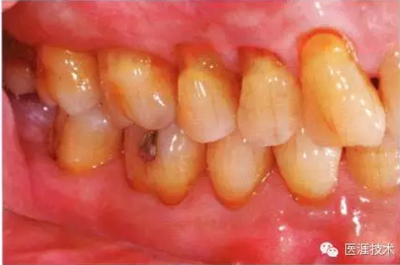

患有牙周病的牙周組織的臨床照片

上海品瑞邁格磁致伸縮治療儀

56歲牙周炎男性的臨床照片

正在服用高血壓藥中的56歲男性。菌斑控制得不好。通過牙周探診,全頜有4~6mm的牙周袋,在X光片中可以看到全頜中度牙槽骨吸收,磨牙處一個地方是重度牙槽骨吸收。通過比較牙周病進展狀態(tài),邊緣部有大范圍浮腫(發(fā)紅、腫脹),和纖維性肥厚。這也可能是服用中的降壓藥的副作用導致的。因為牙齦、牙槽骨比較厚,牙齦呈架子狀。